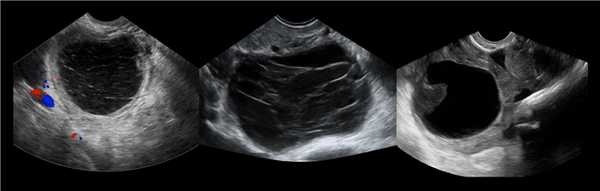

- Ультразвуковое исследование. На УЗИ геморрагическая киста выглядит как однокамерное образование с гиперэхогенными включениями.

- Допплерометрия. Кровоток внутри не определяется. При геморрагическом образовании желтого тела при обследовании видно «огненное кольцо» - характерный кровоток вокруг кисты.